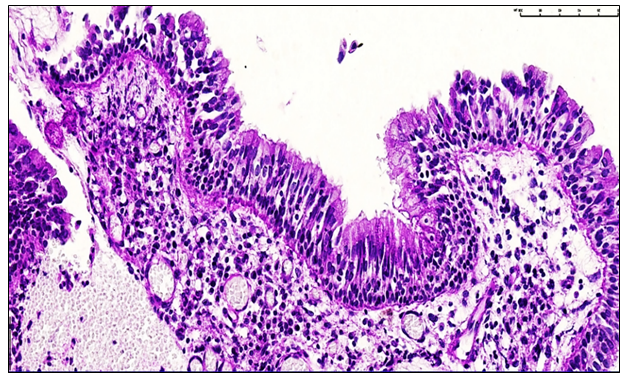

During our study, the clinical and pathomorphological changes in post-traumatic nasal polypoid rhinosinusitis were systematically analyzed. Chronic inflammation of the nasal mucosa led to epithelial metaplasia, lymphocytic and eosinophilic infiltration in the stroma, and fibrotic remodeling. These processes contributed to polypoid overgrowth and partial obstruction of the airways.An allergic background was identified in 23.3% of patients, indicating a chronic course and type III hypersensitivity involvement. Age was a significant factor, with the highest incidence observed in patients aged 18–44 years, which may be associated with active lifestyle, physical activity, and domestic injuries.The progression of polypoid rhinosinusitis was categorized according to the post-trauma period: Group 1 (1–1.5 years), Group 2 (1.5–3 years), Group 3 (3–5 years), and Group 4 (≥5 years). The majority of patients (Group 1, 24%) demonstrated predominant serous inflammation, low density of stromal fibers, and ongoing fibrotic changes.Microscopic and clinical analyses confirmed the main pathogenetic features of polypoid rhinosinusitis: mucosal polypoid overgrowth, epithelial metaplasia, stromal lymphocytic and eosinophilic infiltration, and congestion of small blood vessels. These alterations resulted in airway obstruction and impaired mucociliary clearance.Group 1 (1.0–1.5 years post-nasal trauma): Patients presenting within 1.0–1.5 years after nasal tissue injury accounted for 24% of the study cohort. Morphologically, the nasal mucosa demonstrated predominant serous inflammation, a low density of fibrous structures within the stromal layer, ongoing granulation tissue formation, and sparse fibrotic changes in the connective tissue, indicating early-stage reparative and adaptive processes. (see Figure 4). | Figure 4. Chronic polypoid rhinosinusitis, 1.5 years post-nasal trauma. Focal epithelial hyperplasia and lymphoid cell infiltration are observed in the mucosal lining, with sparse neutrophils. Interstitial edema is present among lymphocytes in the glandular stroma. Staining: H&E, magnification ×100 |